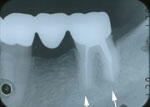

5.15年後

約15年後です。

起こして来た歯(右端)の周りに、骨がしっかりと出来ています。

また、この歯の、近心(左)根の根尖部も、きれいに回復しています。

この起こした歯の遠心根(右の根)の根尖から薬(ポイント)が、少し出ていたのです

が、15年後の写真では、吸収されたのか、なくなっています。

人体の不思議ですね。